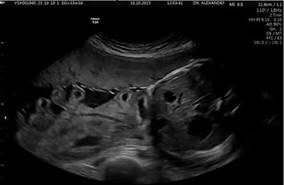

Paciente de 17 años de edad, primigesta, a quién se le realizó el diagnóstico de gastrosquisis fetal en el primer trimestre del embarazo. Acudió posteriormente con embarazo de 38 semanas de gestación con trabajo de parto en fase latente, al rastreo ecográfico se encontró Restricción de Crecimiento Intrauterino (RCIU) tipo 1, líquido amniótico con Bolsillo Vertical Máximo (BVM) de 5 cm, un defecto de pared abdominal de 20 mm en su diámetro transverso con protrusión únicamente de asas intestinales, con una distensión de 28 mm y un grosor de 2 mm de la pared intestinal. Figura 1.

Figura 1. Imagen por ecografía; donde se observa corte axial a nivel abdominal con presencia de defecto ventral con presencia de asas intestinales flotantes sin presencia de dilatación